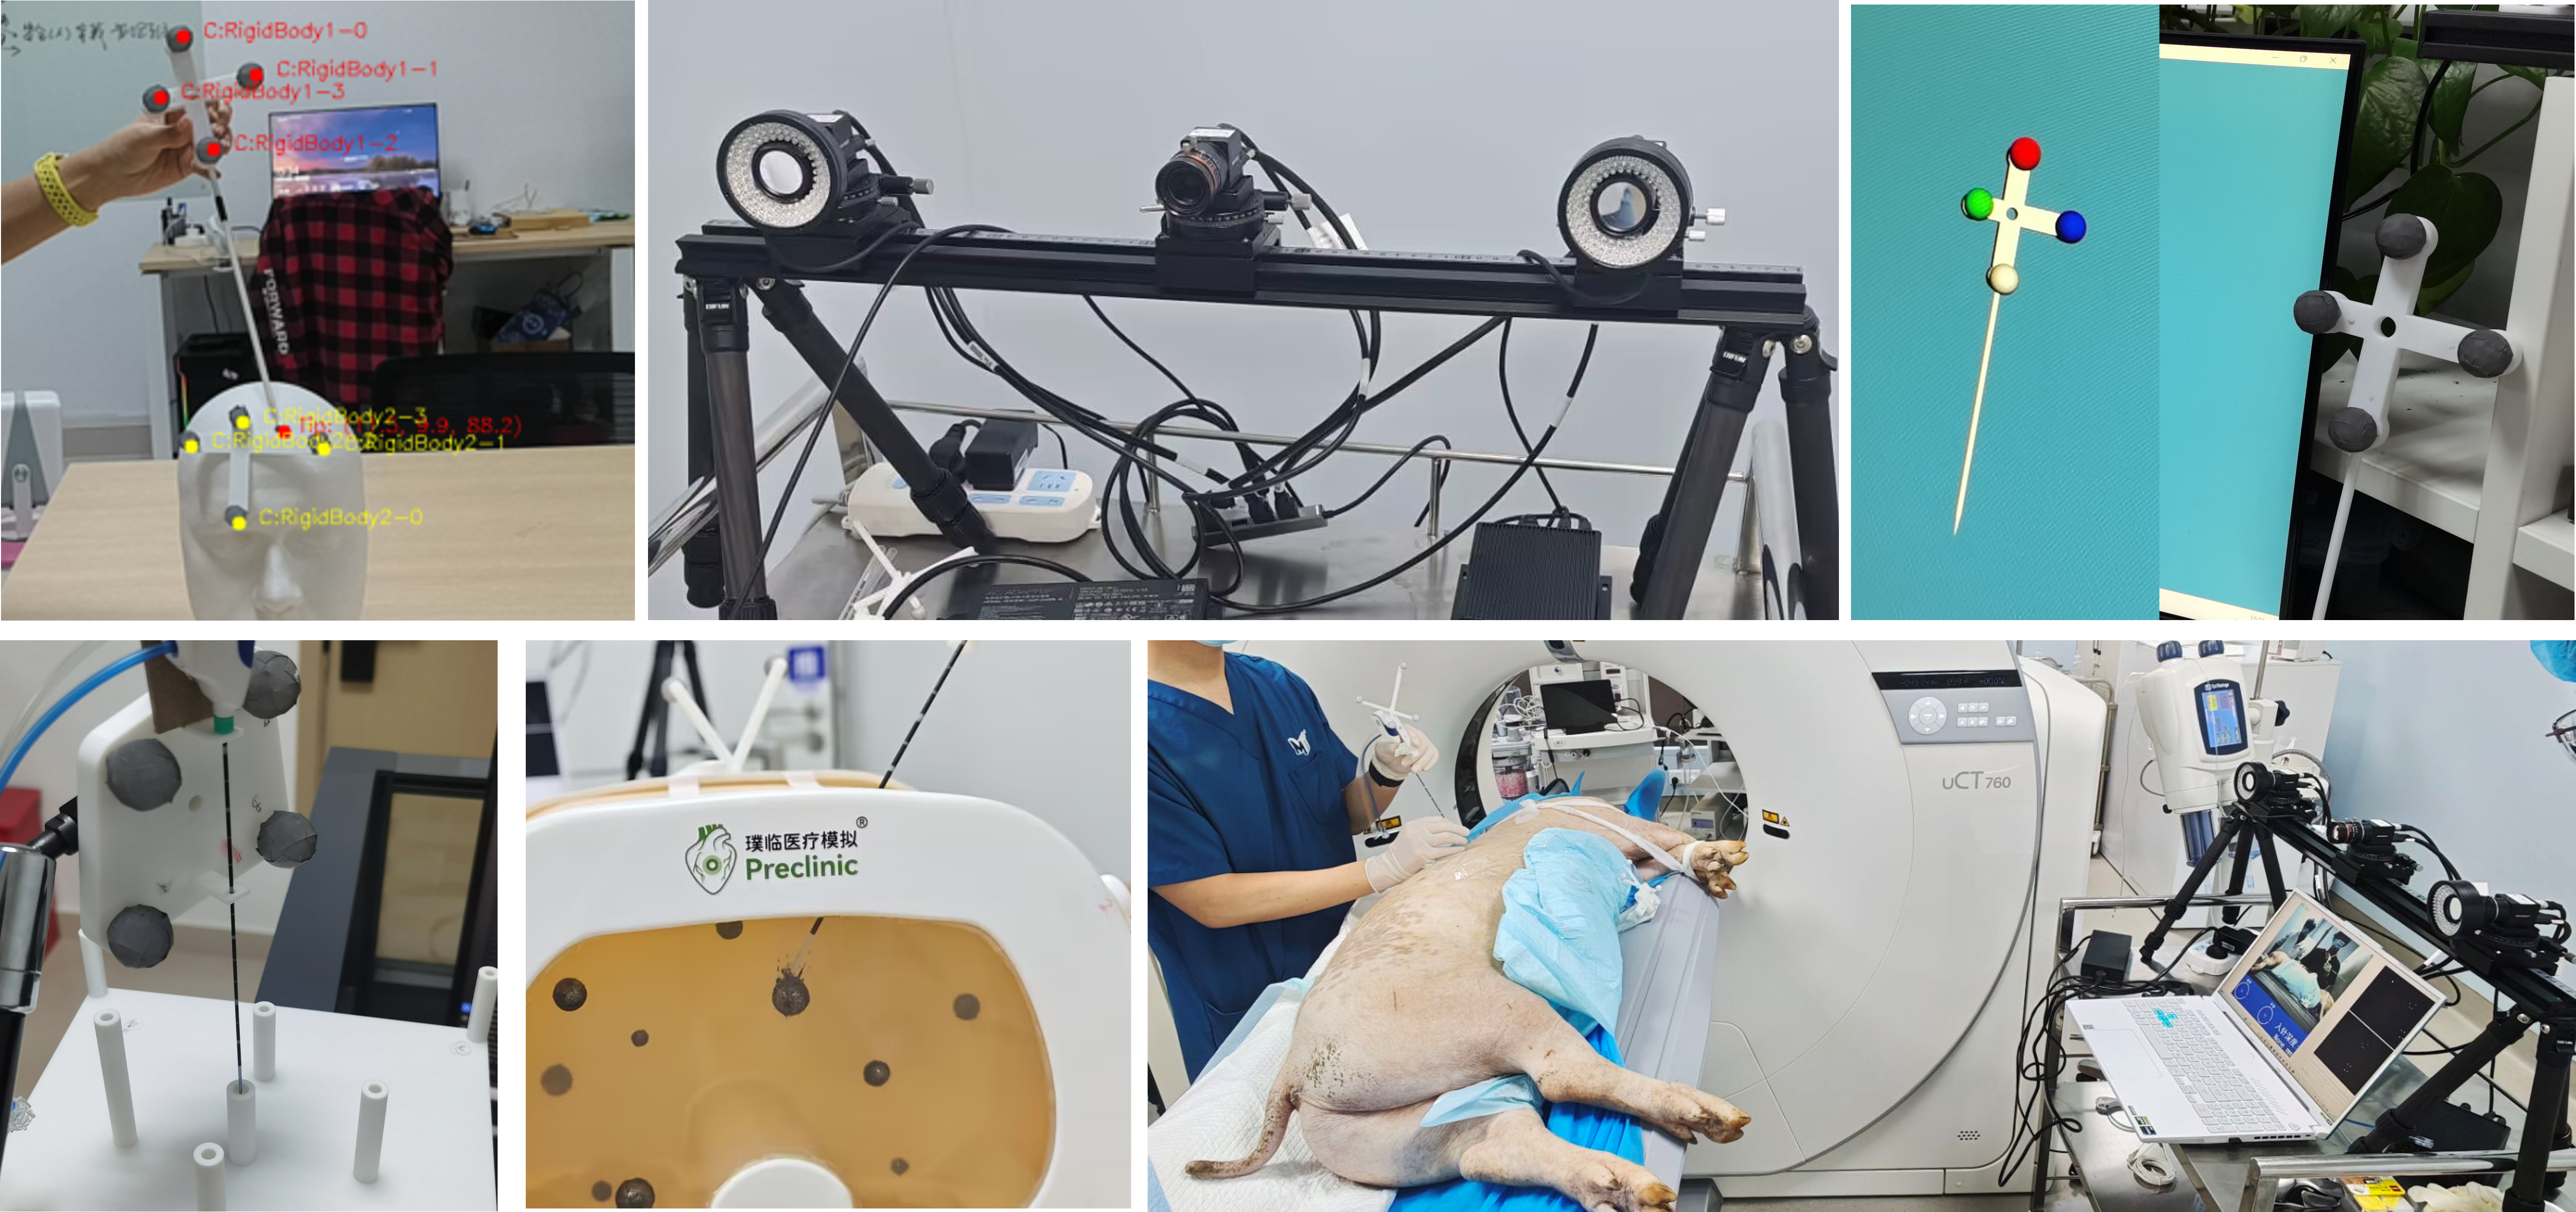

方向二:手术导航设备

在手术导航装置领域,我们的工作集中在开发能够提供实时、精确操作指导的系统。通过整合高质量的医学影像处理技术和精密的空间定位技术,实现对病灶位置及其周围解剖结构的三维重建和可视化展示,从而大幅提升手术精度和安全性。此外,我们也引入增强现实(AR)技术进一步优化用户体验,使得复杂手术过程更加直观和易于操作。

1. 储嫣等,基于体表动态投影与视角自适应机制的智能手术导航系统,国家三等奖,第十九届“挑战杯”竞赛中国科技青年科技创新“揭榜挂帅”擂台赛,2025年(学科竞赛,本科生排名第一)